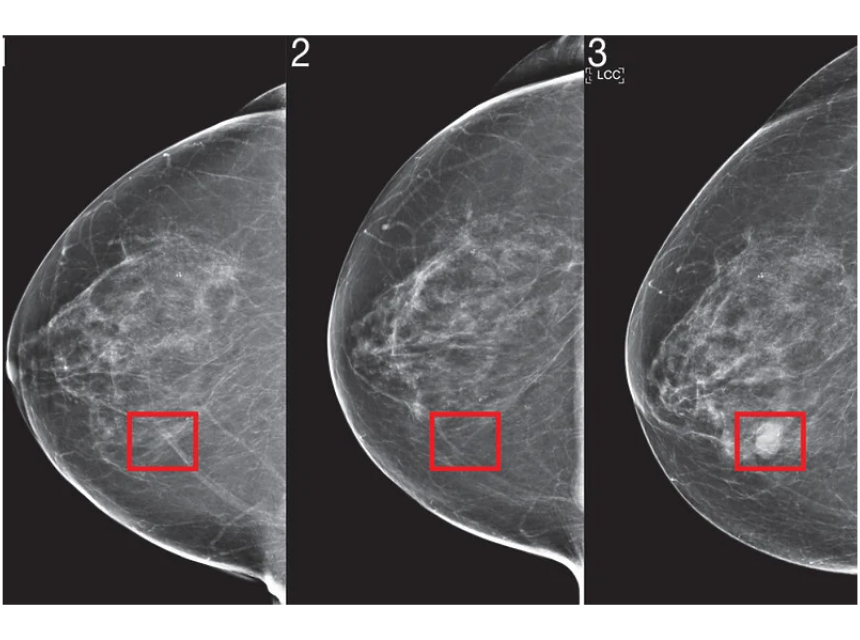

MIT je koristio umjetnu inteligenciju kako bi predvidio razvoj raka dojke. Na fotografijama modela koje proizvodi moguće je vidjeti dio tkiva koji je identificiran kao područje visokog rizika koji je četiri godine kasnije prerastao u karcinom.

Foto: MIT